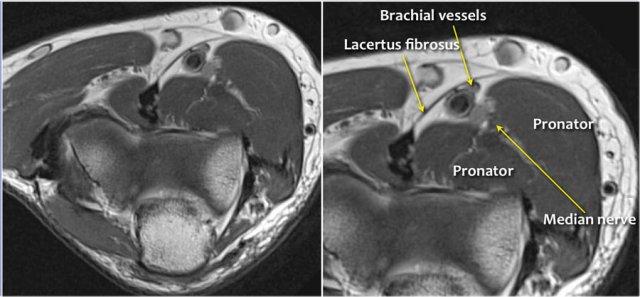

Median nerve

Dây thần kinh giữa đi xuống phía sau Lacertus fibrosis, là cân cơ của cơ nhị đầu và xuyên qua cơ sấp tròn.